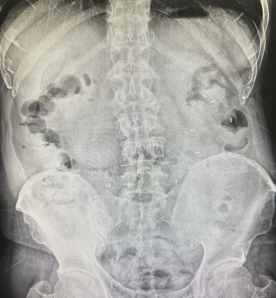

精准诊断:胃肠道传输实验——追踪食物的“旅程”!方松山主任反复强调:“慢传输型便秘的诊断,不能靠猜,必须靠证据。” 在科室,胃肠道传输实验是诊断慢传输型便秘的“金标准”。

现场直击:在读片灯前,方主任正在向李伯伯展示一组特殊的腹部平片。片中清晰可见许多标记物滞留在结肠区域。